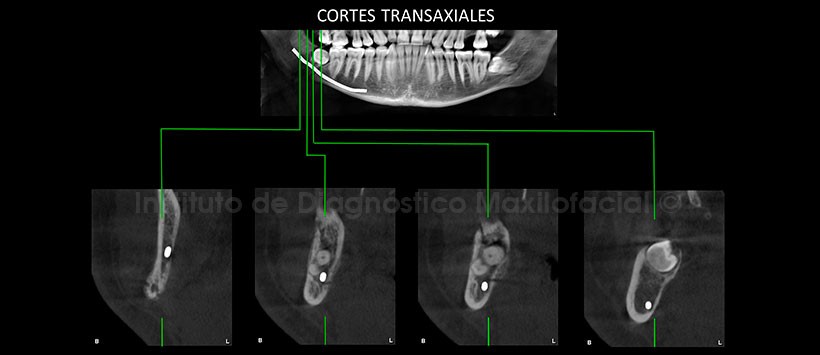

A la evaluación de la tomografía volumétrica de haz cónico (figura 2), apreciamos una fractura ósea la cual compromete ambas corticales óseas. En los cortes transaxiales y tangenciales evidenciamos que dicha fractura condiciona la formación de una leve reacción periostal en la tabla ósea lingual y compromete las corticales del conducto dentario inferior. (Figura 3 y Figura 4)